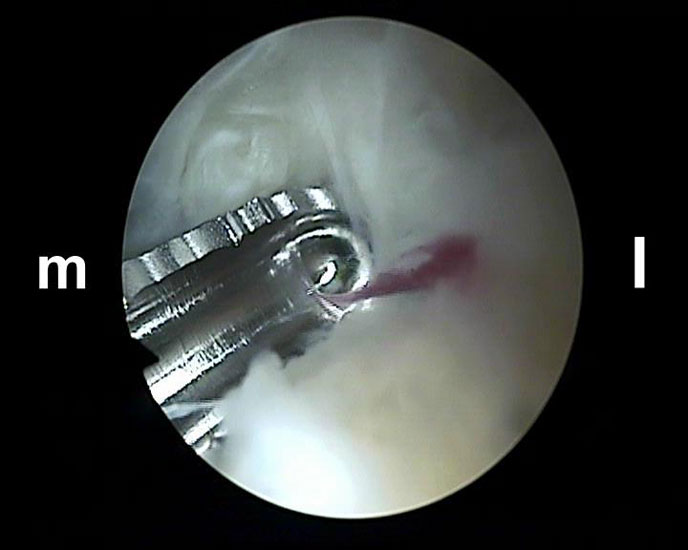

Über das laterale Portal wird ein 4,0 mm Arthroskop senkrecht nach ventral eingebracht mit der Zielrichtung auf den 1. Interdigitalraum. Zur Orientierung kann mit dem stumpfen Wechselstab zunächst der Kontakt zum Knochen getastet werden. Es lassen sich so auch die dorsale Tibiakante, der Proc. posterior des Talus und die craniale Begrenzung des Kalkaneus identifizieren. Ist das Arthroskop über das laterale Portal eingeführt, wird die Blickrichtung nach lateral ausgerichtet. Von medial wird ein Weichteilshaver eingeführt, dessen Arbeitsöffnung nach ebenfalls lateral weist. Die Instrumente werden in der Weise trianguliert, dass die Shaverspitze unmittelbar vor dem Arthroskop identifiziert werden kann (rechte Seite, m=medial, l=lateral).